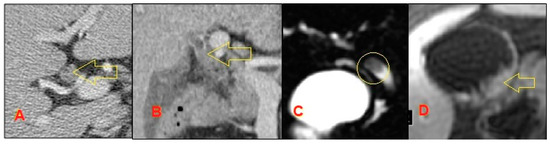

5. Non-Invasive Imaging Studies

- Feldman, M.K.; Coppa, C.P. Noninvasive imaging of the biliary tree for the interventional radiologist. Tech. Vasc. Interv. Radiol. 2015, 18, 184–196. [Google Scholar] [CrossRef]

- Baron, R.L.; Tublin, M.E.; Peterson, M.S. Imaging the spectrum of biliary tract disease. Radiol. Clin. 2002, 40, 1325–1354. [Google Scholar] [CrossRef]

- Singh, A.; Gelrud, A.; Agarwal, B. Biliary strictures: Diagnostic considerations and approach. Gastroenterol. Rep. 2015, 3, 22–31. [Google Scholar] [CrossRef] [PubMed]

- Rösch, T.; Meining, A.; Frühmorgen, S.; Zillinger, C.; Schusdziarra, V.; Hellerhoff, K.; Classen, M.; Helmberger, H. A prospective comparison of the diagnostic accuracy of ERCP, MRCP, CT, and EUS in biliary strictures. Gastrointest. Endosc. 2002, 55, 870–876. [Google Scholar] [CrossRef] [PubMed]